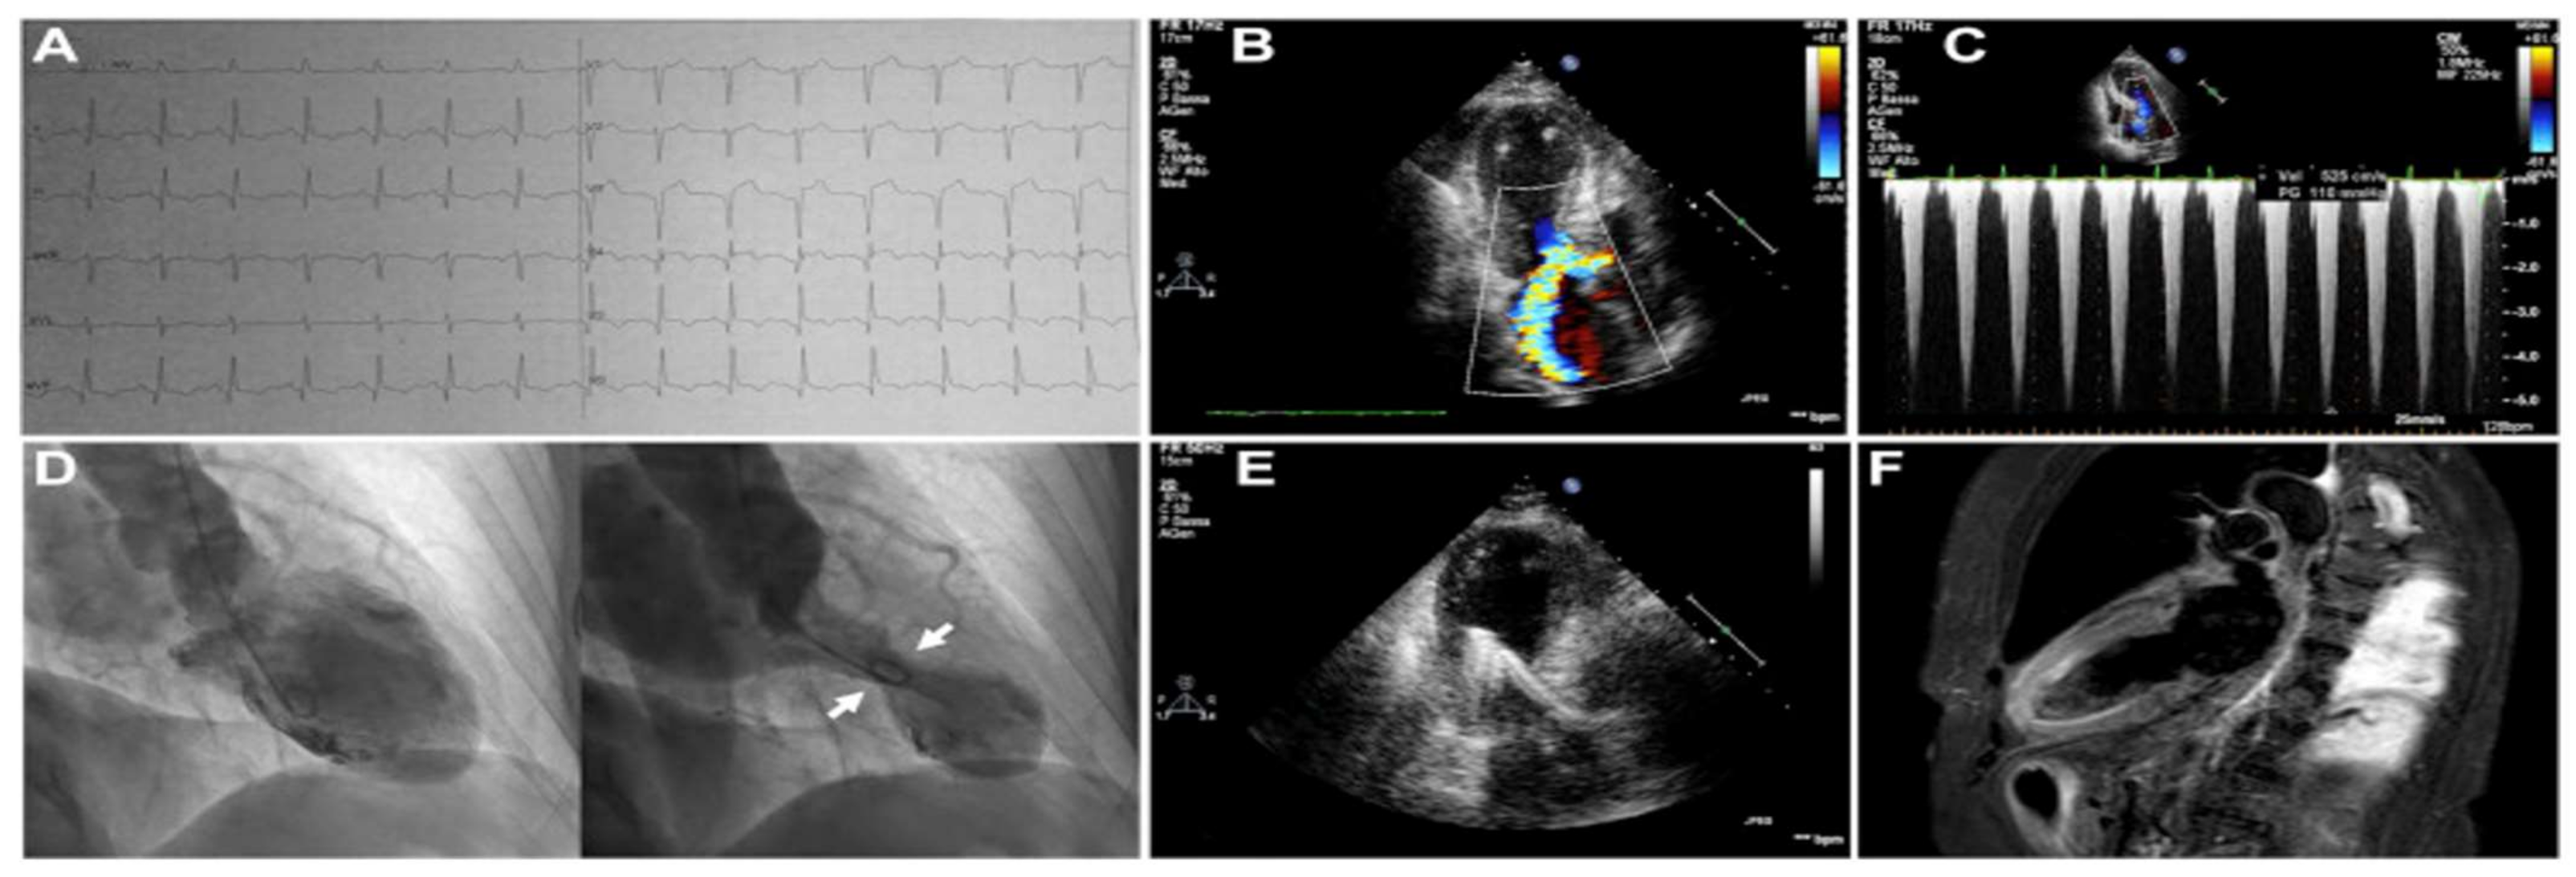

3.11. Mitral Regurgitation in Patients with TTS

3.12. Right Ventricular Involvement in Patients with TTS

3.9. Left Ventricular Outflow Tract Obstruction in Patients with TTS